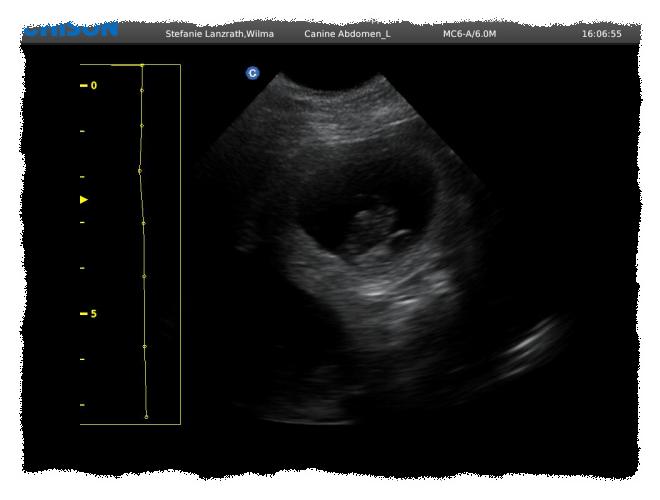

22.06.2020: Wir waren heute mit Wilma beim Ultraschall! Wir

haben viele, kleine Babys im Bauch gesehen! :-) Somit erwarten wir unseren

B2-Wurf um den 25.07.2020! :-)